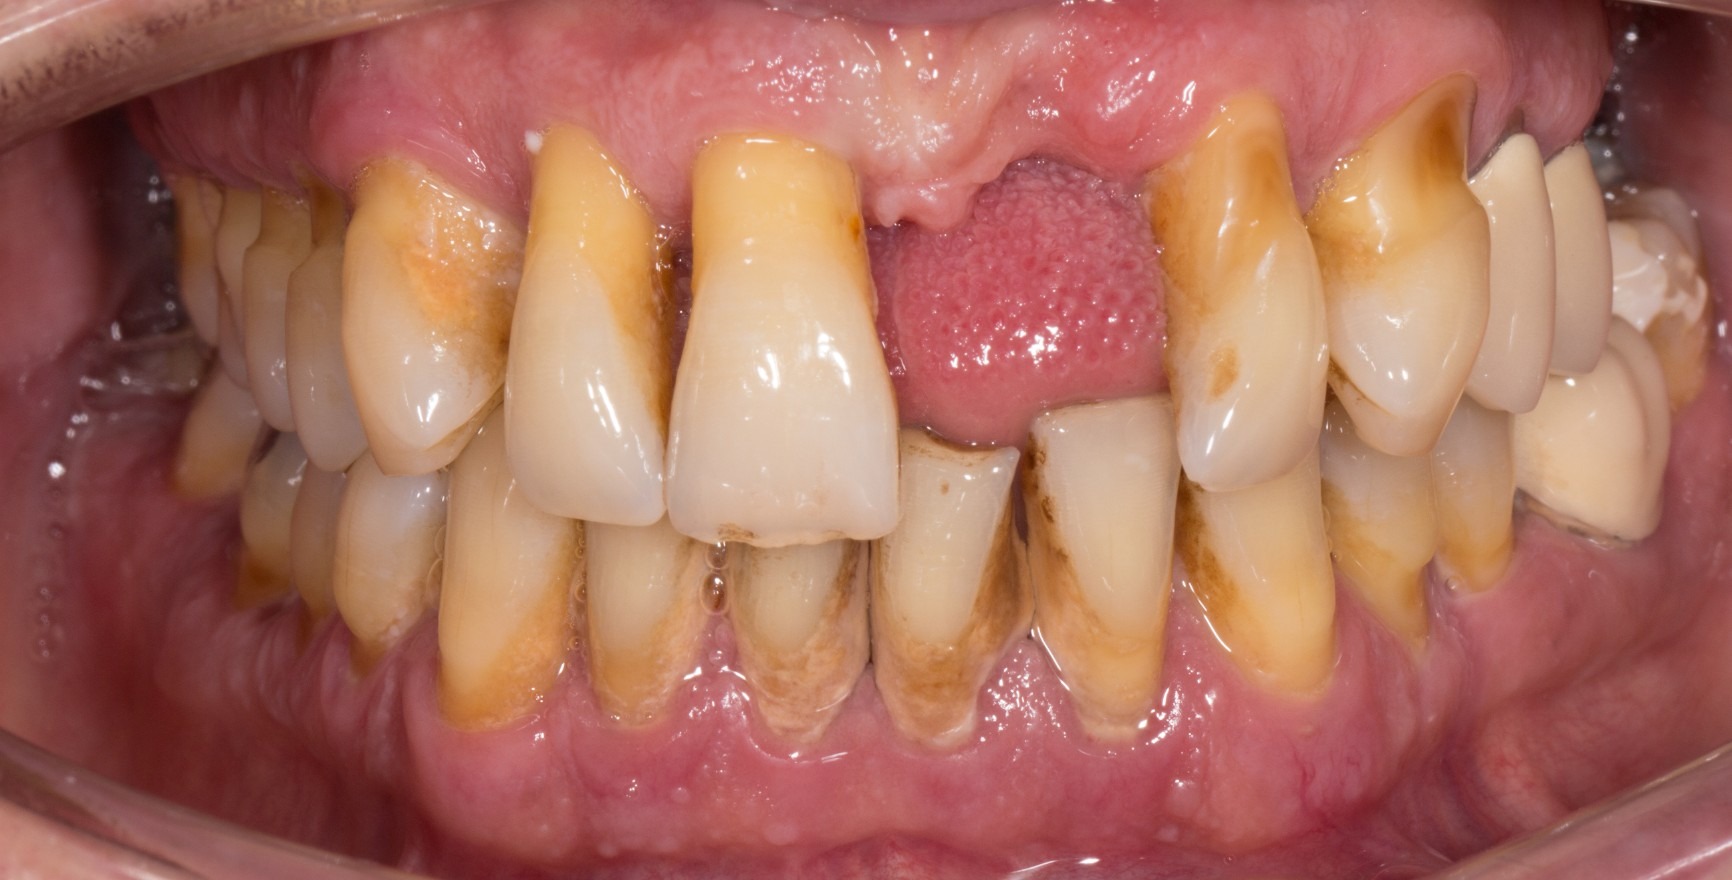

Състоянието на клинично пародонтално здраве на интактен пародонт се разграничава от това на редуциран пародонт, който вече е засегнат от клинична загуба на прикрепване. Тази загуба на прикрепване може да настъпи:

в резултат на възпаление в хода на пародонтита. Клиничното пародонтално здраве описва стабилното състояние след успешно приключване на пародонталното лечение.

Клиничният критерий винаги е липсата на кървене при внимателно сондиране (кървене при сондиране = BoP). Прави се разграничение между специфична за мястото/зъба диагноза с липса на BoP на съответното място на измерване и специфична за пациента диагноза, при която прагова стойност на BoP ≤ 10 % все още отговаря на критериите за клинично пародонтално здраве. Дълбочината на сондиране не трябва да надвишава 3 mm. При намален пародонт след пародонтално лечение прагова стойност от 4 mm все още се счита за стабилно състояние (Matuliene et al., 2008).